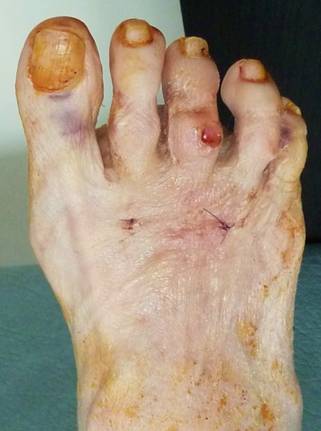

Судя по фотографиям, укорочение 2 пальца не является косметически значимым. Есть его молоткообразная деформация наряду с варусным отклонением 3 пальца, который уже "подлез" под второй, и вальгусной деформацией дистальной части 1 пальца (hallux valgus interphalangeus). То есть, расстояние между 1 и 3 пальцами уменьшено. Значит вмешательство должно быть направлено не только на устранение молоткообразной деформации 2 пальца, но и на формирование пространства для него между 1 и 3. Оптимальным мог бы быть следующий набор хирургических действий: чрескожная удлиняющая тенотомия разгибателей и поверхностного сгибателя 2 пальца; коррегирующие чрескожные остеотомии оснований основных фаланг 2 и 3 пальцев и дистальной трети основной фаланги 1 пальца. Если не оперируете чрескожно, операции на 2 и 3 пальцах можно сделать через маленькие разрезы узкой пилкой или узким долотом, а на 1 пальце любым доступным Вам способом. Фиксировать или нет остеотомии зависит от Ваших предпочтений. При правильно наложенной и удерживаемой в течение 3-4 недель повязке внутренняя фиксация таких остеотомий не обязательна. Операция на трех пальцах выгодна еще и тем, что позволит пропорционально укоротить их, сохранив имеющееся взаимоотношение длин.

Что видим: укорочение 2 плюсневой кости, лёгкую молоткообразную деформацию 2 пальца, незначительное варусное отклонение 3 пальца. И всё! Длина 1 пальца, длины всех остальных плюсневых костей симметричны (померяйте с линейкой физическую длину – она отличается в пределах 2 мм, т. е. в пределах погрешности измерения и рентгенологической позиции). Hallux valgus’а нет никакого, даже interphalangeus (посмотрите на другую стопу). Диагноз: брахиметатарзия 2 плюсневой кости. Соответственно, нужно эту самую кость удлинять. А не укорачивать (разворачивать, отклонять) соседние кости!!! Этими вмешательствами даже теоретически невозможно решить проблемы пациентки, а ведь у каждой операции есть последствия и риски.

Пациентку, скорее всего, беспокоит косметический дефект. И молоткообразная деформация 2 пальца - уже есть гиперкератоз на тыле проксимального межфалангового сустава. Варусное отклонение 3 пальца возникло компенсаторно, оно минимально и, скорее всего, пациентку не беспокоит.